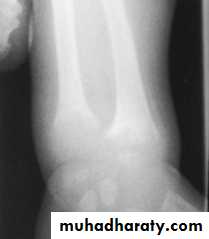

Widening of the wrist

1.Clinical2.X-ray of the wrist :will show characteristic radiographic changes of the distal ulna &radius include :

.widening

.concave cupping &fraying (poorly demarcated ends ).

.There is increased distance between the distal ends of radius &ulna &the metacarpal bones .

Radiological changes of rickets